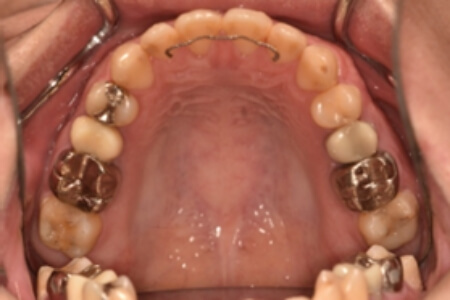

| 治療内容の詳細 | 初診時26歳の男性で、受け口を気にされ来院されました。 検査の結果、下顎前突、上顎前歯部叢生および上顎側切歯反対咬合を伴うアングルⅢ級不正咬合と診断しました。 先ず、前期治療として、リンガルアーチを使用し、上顎中切歯を前方へ移動させ、反対咬合の改善を行いました。 その後、マウスピース型矯正装置(インビザライン)で配列を行いました。 治療期間としては1年8か月でした。 |